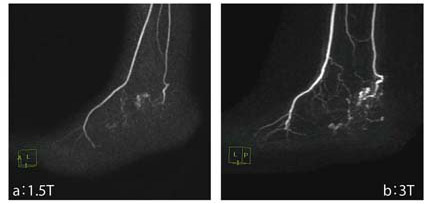

図2 3Tと1.5TにおけるTOF法を用いたMRAの比較

a:(1.5T)TR/TE 29/6.9,マトリックス256×256,NEX1,撮像時間 5分01秒

b:(3T)TR/TE 22/2.8,マトリックス384×224,NEX1,撮像時間 4分46秒

図6に,左足背の血管奇形の描出能を比較提示する。本来は,時間分解能が比較できるため動画が良いのだが,ここでは静止画であることが残念である。

図6 3Tと1.5Tにおける左足背の血管奇形の描出能の比較(4D MRA)

a:(1.5T)TR/TE 4/1.5,FA 35°,スライス厚 1.6mm,NEX1

b:(3T)TR/TE 3/1.7,FA 20°,スライス厚 1.6mm,NEX0.5